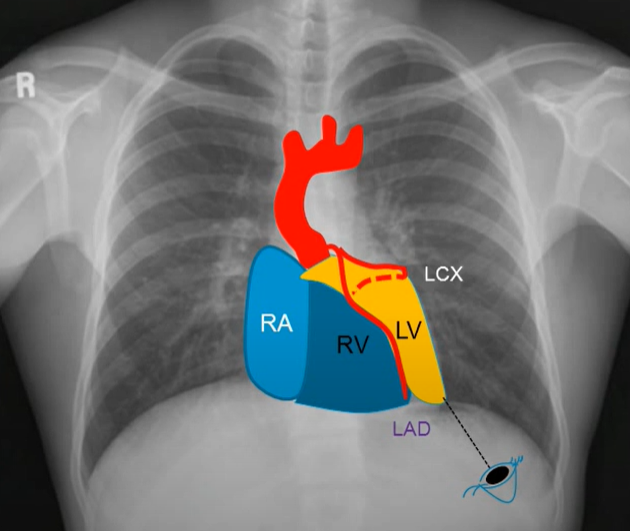

Though we do coronary angiogram and complex angioplasties day in day out, we rarely get oriented , to the exact anatomical relations of individual coronary artery with reference to cardiac chambers. When I asked my fellows, to identify , the chambers on either side of left main at its bifurcation , none of them were confident. (I must confess, I was also in the same page of vagueness till I saw this clip .)

*LMCA after emerging from the aortic sinus, the travels a short distance, usually between 5 to 15 mm, towards the left side of the heart. During this initial course, the LMCA passes posterior to the pulmonary trunk. The left main is also closely related to RVOT especially the posterior and septal aspect. Once bifurcated , the LCX is related to LAA.

LAO caudal view : The most familiar, and usually the first shot we do.

Note : In LAO caudal view, we are looking from the left side, from below near the spleen, towards the right shoulder. The anterior structures will come on the left side and all posterior strictures fall on the right side of the image.

The yellow Zone is a wide area between LAD and LCX that engulfs the whole left ventricle. The blue zone is the anteriorly placed RV, especially the RVOT, which comes closer to the left main. The one below the LCX is the posteriorly placed left atrium depicted in green zone. (Not in above picture)

Clinical Implication

As cardiologists, we literally camp inside the coronary arteries with various weaponry and ammunition. It is always wiser to know the surrounding structures, as the risk of Injury hangs like a Damocles sword . Intra-cavity perforation, though rare, can still occur, and many are not recognized because they are well tolerated. Structural interventions like LAA closure and RVOT ablations can directly pose a threat to the left main or LCX, respectively.